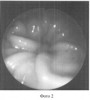

Сущность данного обследования поясняется фотографиями, где:

Фото 2: сомкнутое состояние жома.